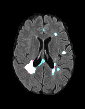

In recent years, data-driven machine learning (ML) methods have revolutionized the computer vision community by providing novel efficient solutions to many unsolved (medical) image analysis problems. However, due to the increasing privacy concerns and data fragmentation on many different sites, existing medical data are not fully utilized, thus limiting the potential of ML. Federated learning (FL) enables multiple parties to collaboratively train a ML model without exchanging local data. However, data heterogeneity (non-IID) among the distributed clients is yet a challenge. To this end, we propose a novel federated method, denoted Federated Disentanglement (FedDis), to disentangle the parameter space into shape and appearance, and only share the shape parameter with the clients. FedDis is based on the assumption that the anatomical structure in brain MRI images is similar across multiple institutions, and sharing the shape knowledge would be beneficial in anomaly detection. In this paper, we leverage healthy brain scans of 623 subjects from multiple sites with real data (OASIS, ADNI) in a privacy-preserving fashion to learn a model of normal anatomy, that allows to segment abnormal structures. We demonstrate a superior performance of FedDis on real pathological databases containing 109 subjects; two publicly available MS Lesions (MSLUB, MSISBI), and an in-house database with MS and Glioblastoma (MSI and GBI). FedDis achieved an average dice performance of 0.38, outperforming the state-of-the-art (SOTA) auto-encoder by 42% and the SOTA federated method by 11%. Further, we illustrate that FedDis learns a shape embedding that is orthogonal to the appearance and consistent under different intensity augmentations.